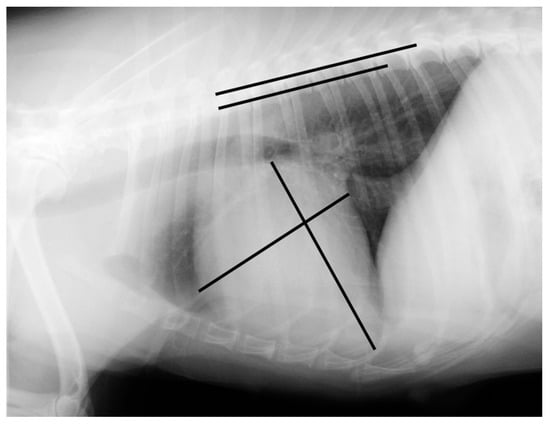

Measurements were made using an adjustable calliper in millimetres, which was then converted to vertebral units (v) exact to 0.1 v, according to the method described by Buchanan and Bucheler [4]. All of the measurements were performed by the same examiner (EC) using DICOM PACS view radiography computer software (Synapse, Fuji, Tokyo, Japan). In the right lateral radiograph, the long axis of the heart was measured from the ventral border of the left main stem bronchus to the most distant contour of the cardiac apex (L). The maximal short-axis of the heart was measured perpendicular to the long-axis (S). The two measures were repositioned over thoracic vertebrae beginning with the cranial edge of T4, using an adjustable calliper (Figure 1 and Figure 2).

Figure 1. Measurement of the vertebral heart scale in a right lateral radiograph illustrating an example of a vertebral heart scale in a Brittany Spaniel of 10.8 v (the image was acquired using a PICKER CONVIX 80–UNIVERSIX 120 device (Picker International, Uniontown, OH, USA); the kVp, mA, and time settings were not recorded). Two lines are drawn on the heart to measure its long and short axes. They are then transposed onto the spine and recorded as the number of vertebrae beginning with the cranial edge of T4. These values are estimated to one decimal place and added to obtain the vertebral heart size.